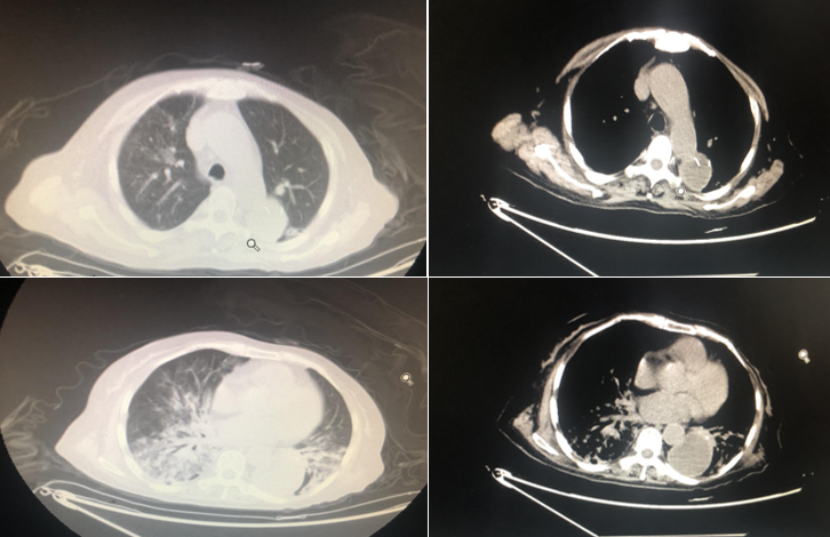

病史情况:85岁男性患者,体重90 kg。2023年10月20日第1次入住我院呼吸科。主诉:反复发热伴咳嗽1月余。患者1月前出现发热,最高38.8℃,伴咳嗽咳痰,黄白痰,至我院高新院区内科就诊,完善胸部CT及支气管镜灌洗,考虑肺部感染,先后予左氧氟沙星、头孢哌酮舒巴坦、美罗培南、替加环素、利奈唑胺等抗感染,仍反复发热,且大便不解,考虑肠梗阻,至我科就诊。

辅助检查:①血常规:WBC 15.73×109/L,Hb 90 g/L,PLT 21×109/L,幼稚细胞百分比15%。②生化:谷丙转氨酶22 U/L,白蛋白25.5 g/L,肌酐139.1 μmol/L,葡萄糖7.14 mmol/L,血钾3.9 mmol/L,钠135.4 mmol/L。③入科炎症指标:PCT 4.9 ng/ml,CRP 168.16 mg/L。④入科胸部CT示双肺多发感染,左肺为著。⑤血气分析(吸氧5 L/min):pH 7.43,PaCO2 41 mmHg,PaO2 65 mmHg,Lac 2.3 mmol/L。

入院诊断:呼吸衰竭,重症肺炎,MDS(EBⅡ),鲍曼不动杆菌感染。

治疗方案:头孢哌酮舒巴坦(3.0 g q8h微量泵入),依拉环素100 mg q12h ivgtt,高流量湿化氧疗,加强院感防护。

治疗效果:患者CRP和PCT显著下降(图6)。后转血液科进行MDS相关治疗。